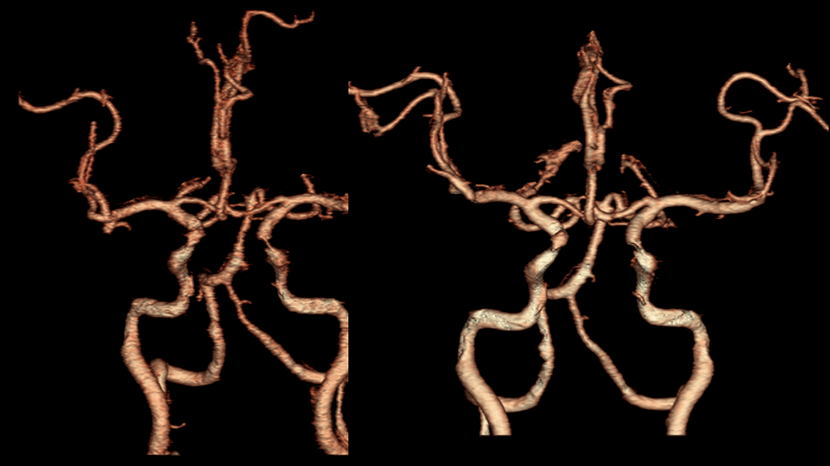

CT혈관 조영술과 뇌혈관조영술에서 좌측 중대뇌동맥의 폐색이 보임

혈관내 수술 기법으로 혈관안에 있는 혈전을 제거

수술전 사진과 비교시, 사라졌던 혈행이 되살아남